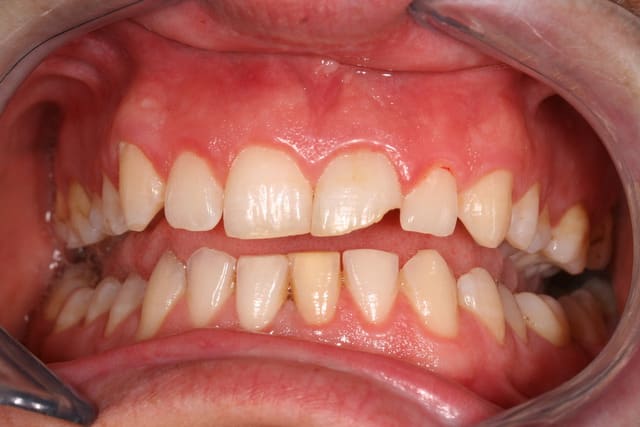

tableau clinique : patiente 25 ans-13 très foncée par nécrose pulpaire sans carie (choc?occluso?)-aucune atteinte de l'émail

objectif : rattrapage de la teinte

déjà tenté : acide extérieur -sans résultat probant

Tu peux faire une gouttière unitaire et utiliser du peroxyde de carbamide à 15% (et pas acid) en port nocturne.

Exemple d'un cas.